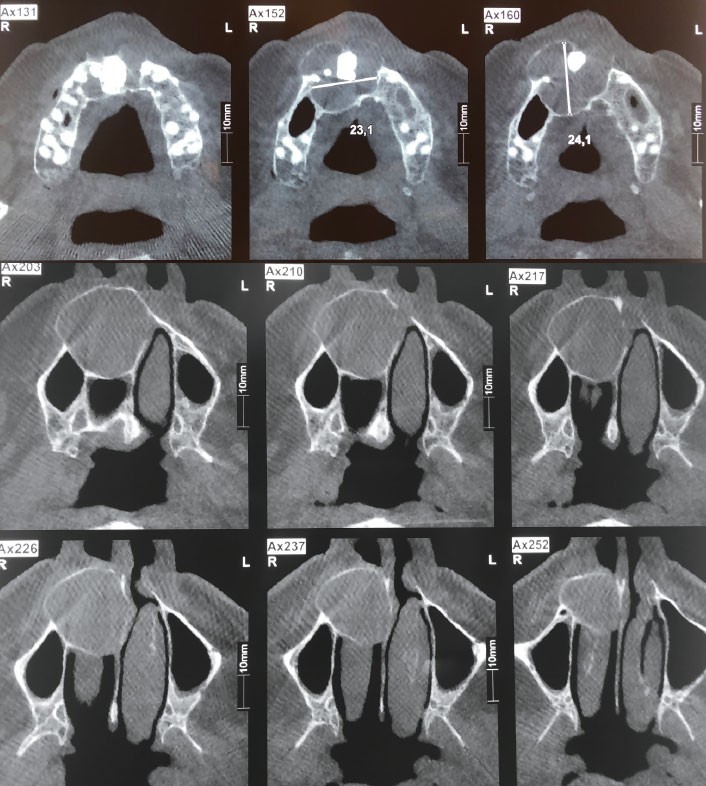

2. Le diagnostic de lésion kystique maxillaire étant posé, un examen tomodensitométrique est réalisé. Il met en évidence un volumineux kyste maxillaire antéro latéral droit (fig. 2 et 3).

Il existe :

a. une dent incluse

b. une lyse du plancher de la fosse nasale droite

c. une extension vers le sinus maxillaire droit

d. une lyse osseuse palatine